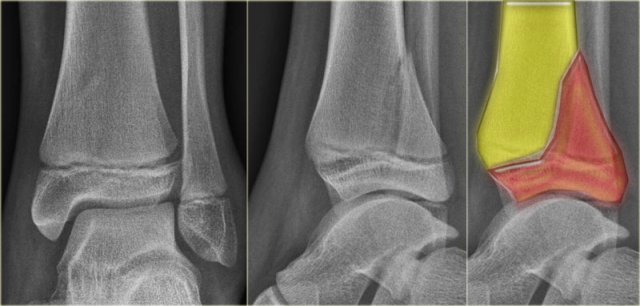

The x-ray shows a subtle Tillaux fracture, which is better appreciated on the CT-images.

Study these images carefully and remember the stages of an exorotation injury.

What is going on here?

There is a Tillaux fracture due to avulsion of the anterolateral part of the distal tibia by the anterior syndesmosis.

This can be a stage 2 of a Weber C fracture.

Stage 1 is rupture of the medial collateral ligaments and stage 3 is a fibula fracture above the level of the syndesmosis.

So now we start looking for stage 4, which is rupture or avulsion of the posterior syndesmosis.

Do you now see the tertius fracture on the axial CT-image?

This patient has an unstable ankle injury and a syndesmotic screw needs to be inserted.